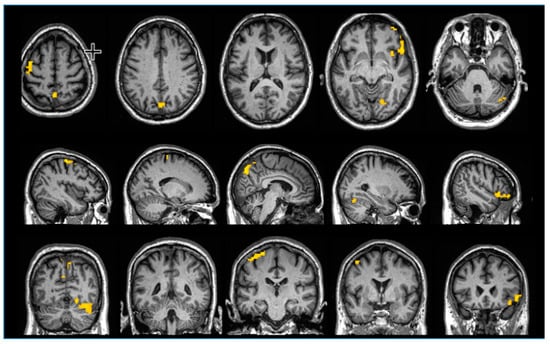

2.2. Coma Scale and fMRI

2.4. MRI Parameters